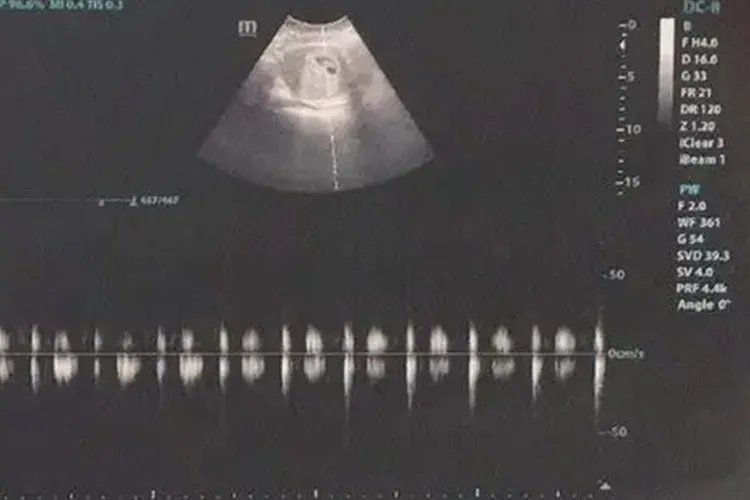

概述怀孕40天左右约为孕6周,属于孕早期,B超下可见胚芽和原始心管搏动。孕6周时,孕妇可出现黑加征、早孕反应等情况,尤其要注意孕妇的身体情况。B超表现妊娠6周时,B超可见到胚芽和原始心管搏动。

怀孕早期B超检查的主要目的是确定宫内妊娠,排除异位妊娠、滋养细胞疾病、盆腔肿块等。若为多胎,可通过胚囊数目和形态判断绒毛膜性。停经35日时,宫腔内见到圆形或椭圆形妊娠囊;妊娠6周时,可见到胚芽和原始心管搏动,妊娠11-13周测量胎儿头臀长度能较准确地估计孕周,校正预产期。其他表现妊娠6-8周时,双合诊检查子宫峡部极软,感觉宫颈与宫体之间似不相连,称为黑加征。孕妇在停经6周左右还可能会出现流涎、乏力、嗜睡、食欲缺乏、恶心、晨起呕吐等症状,称为早孕反应,部分患者有情绪改变。多在停经12周左右自行消失。此外孕妇还会出现停经、尿频、乳房胀痛等情况。注意事项孕早期是胚胎形成阶段,所以也可称为胚胎期。这一时期最重要的就是要避免有害因素对胚胎的影响。要注意以下几点:正确认识妊娠反应是一种生理现象,不必过分紧张。要保证休息,鼓励进食。必要时服用维生素B6、B1,乳酶生、胃蛋白酶等。如呕吐严重,不能进食时间过长,应找医生做相应处理;注意营养,提倡孕前和早孕期增补叶酸和多种维生素,鼓励准妈妈多吃蔬菜、水果等;不去拥挤、空气污浊、嘈杂的地方,注意预防感染疾病。远离有毒有害的工作环境,如接触农药、化肥、化学制剂、X射线等的工作。